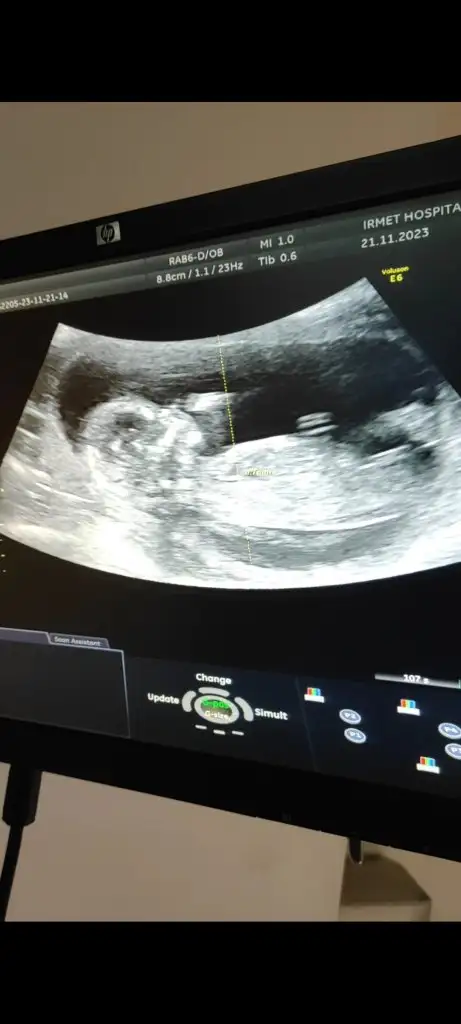

Merhaba ben yeniyim de inşallah gören ya da cevap yazan olur 13 haftalık olduk bugün randevum vardı doktor direk daha erken dedi cinsiyet tahmininde bile bulunmadı çok merak ediyorum acaba tahmin edecek birileri var mi